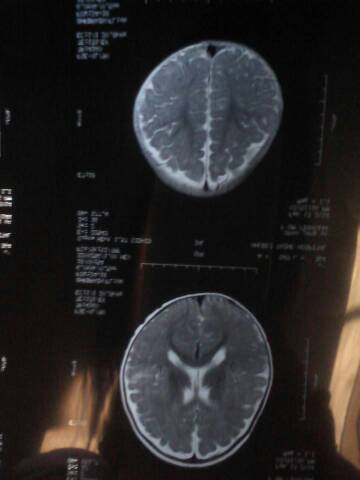

病情分析: 你好,癫痫药物有很多种,苯妥英钠、卡马西平、乙琥胺、丙戊酸钠等称为老抗癫痫药, 指导意见: 其中苯妥英钠、卡马西平、丙戊酸钠是目前广泛应用的一线抗癫痫药。目前;加巴喷丁、拉莫,三嗪、氨已烯酸、托吡酯等,目前比较新的是优时比的左乙拉西坦片。对于明确病因的癫痫,除有效控制发作外要积极治疗原发...